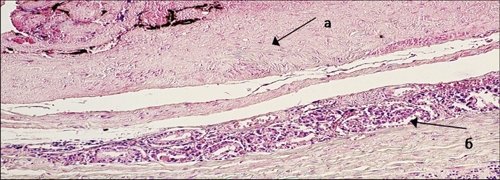

Данная область со стороны капсулы окрашена (индиа-инк), иссечена с подлежащей тканью предстательной железы, направлена на морфологическое исследование. Морфологическое заключение: умереннодифференцированная аденокарцинома, прорастающая капсулу предстательной железы (рис. 5).

Окраска гематоксилином и эозином, цв. 100х.

Окраска гематоксилином и эозином, цв. 200х.